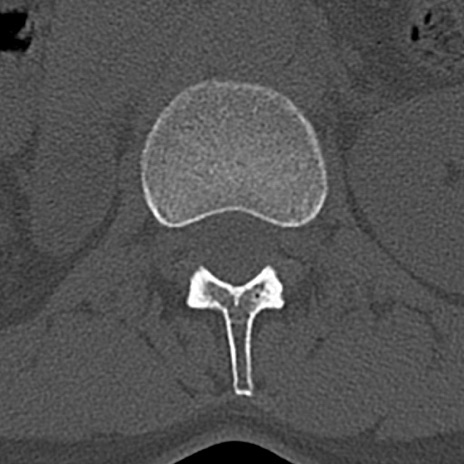

腰椎CT

横断像と矢状断像